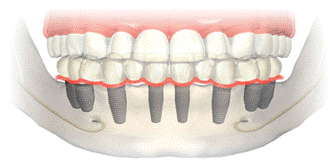

При полном отсутствии зубов в челюсть нужно установить не менее 8 имплантатов-опор, для обеспечения основательного крепления и наиболее длительного сохранения конструкции в исправном состоянии.

Но бывают случаи, когда в предполагаемой области вживления имплантата опорная костная ткань находится в недостаточном количестве, и установка всех 8-и имплантатов крайне затруднительна.

Для таких пациентов возможна имплантация 6 опор для крепления моста.

На верхней челюсти количество имплантатов рекомендуется больше чем на нижней, так как костная ткань имеет более рыхлую структуру.

Важно знать, что малярные группы разделять нельзя, поэтому, при сохранении адекватных свойств кости и прочих условий для имплантации, установка как минимум 8-и имплантатов считается наиболее оптимальным решением для обеспечения правильного функционирования новых зубов.

При этом наиболее предпочтительнее собрать мост на весь зубной ряд из 2-х или 3-х мостовидных конструкций отдельно зафиксированных в челюсти. Это во многом облегчает как домашний гигиенический уход за протезом, так и профессиональное обслуживание протеза у стоматолога, например, если возникнет необходимость в ремонте.